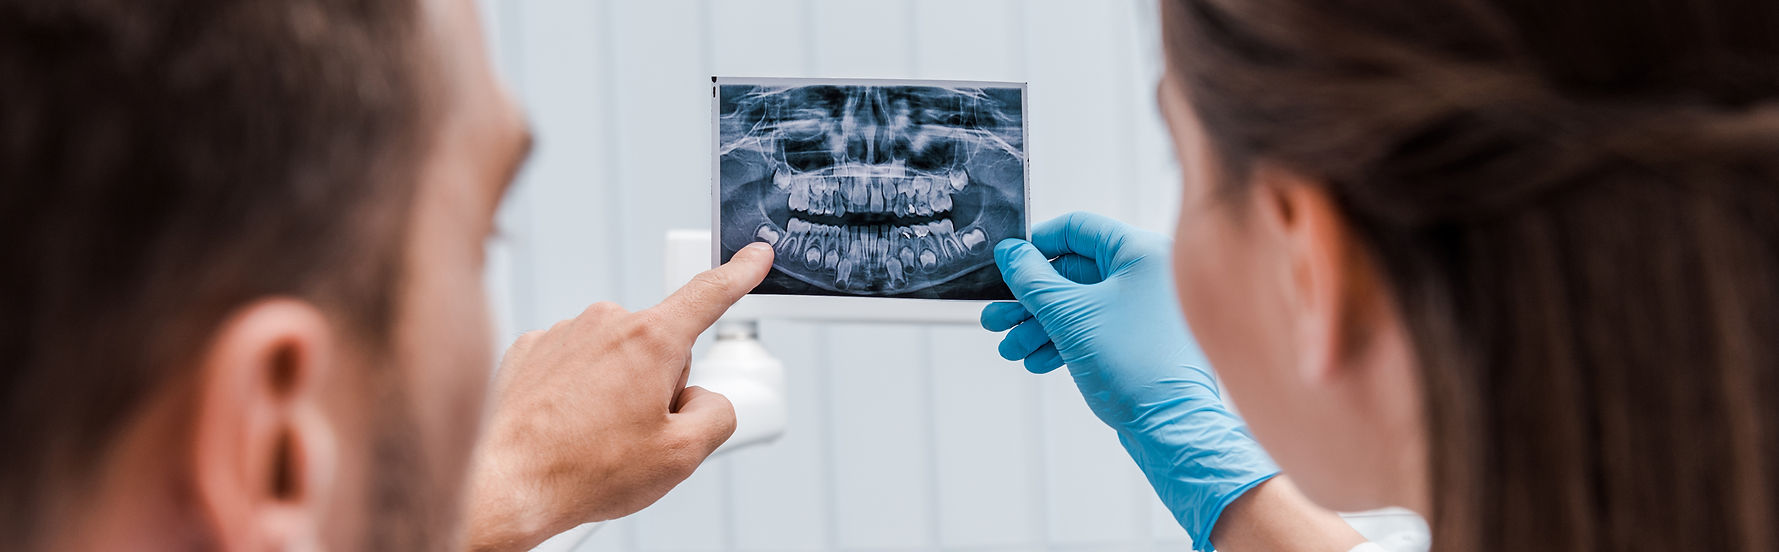

Radiologie dentaire

Il s'agit d'un outil de diagnostic précieux qui permet de déceler de façon précoce une pathologie dentaire et d’anticiper avant même que celle-ci deviennent douloureuse.

La panoramique dentaire permet également d'obtenir un historique sur les différents soins apportés.